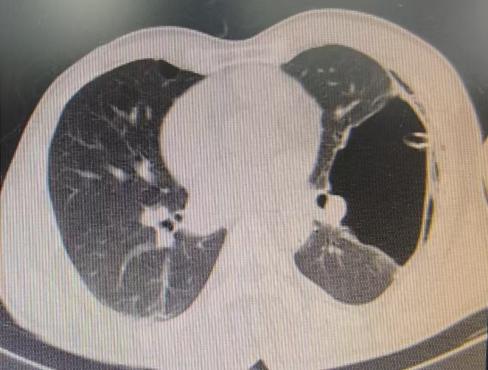

患者信息及手术操作:38岁的李先生(化名)最近总算松了一口气。多年来一直困扰他的左肺巨大肺大疱(76mm×117mm),在澳博娱乐呼吸与危重症医学科专家团队的精心医治下,通过微创手术得到了显著改善。

近期,国内知名呼吸介入专家陈愉教授联合澳博娱乐呼吸与危重症医学科团队,为李先生施行“胸腔镜下肺大疱探查术 + 胸腔闭式引流术”。手术中,陈愉教授运用单孔胸腔镜技术,仅在患者胸壁开了一个1cm的小切口。通过高清胸腔镜系统探查发现,患者胸腔内存在广泛粘连以及多发微小肺大疱,肺叶解剖结构异常,肺门血管直接暴露,经判断肺大疱腔已与胸腔贯通。

面对这一复杂状况,陈教授凭借丰富的经验果断调整手术方案。在确保安全的前提下,对可疑病灶进行了精准活检取样,随后精准置入胸腔引流管。术后即刻CT确认引流管位置良好,同时制定了严密的术后管理方案:每日监测引流量及肺复张情况,若引流量持续减少且肺大疱逐渐缩小,则按计划拨管;若肺大疱未明显缩小,则考虑拔除引流管后转外科进行胸膜剥离术。

术后复查CT显示,肺大疱明显缩小,患者胸闷症状显著减轻。整个手术过程进展顺利,患者术后恢复良好。

(术前左肺肺大疱明显-术后肺大疱逐渐缩小闭合)